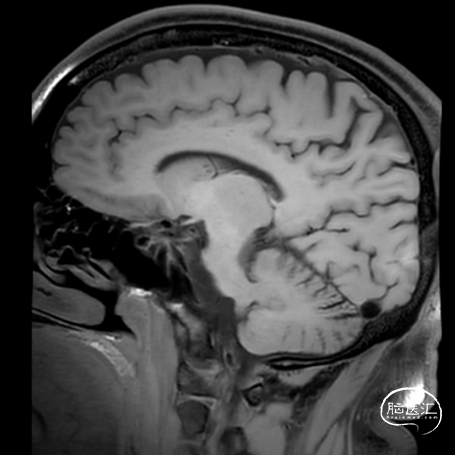

男性,38岁。

主诉:突发头痛、头晕1天。

既往史:无特殊。

查体:GCS 评分14分。

1. 蛛网膜下腔出血

2. 左侧大脑中动脉分叉部动脉瘤